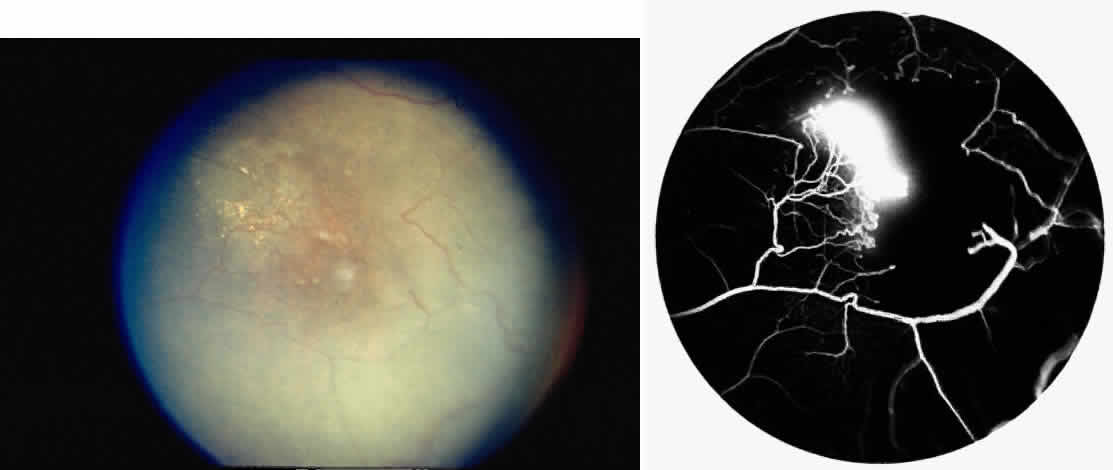

Occlusions of the central retinal artery and major arteriolar branches are probably most frequent in young patients with homozygous sickle cell anemia; however, they may also occur with other sickling genotypes (Fig. 7).39,83,84 They may cause permanent or transient visual loss and can occur simultaneously in both eyes.85–87 Arterial occlusion has also been reported to occur as a complication of retrobulbar anesthesia and following compression of the eye during photocoagulation (Fig. 8).88

Fig. 7. Transient perimacular arteriolar occlusions in a 32-year-old patient with SC disease, who presented with decreased vision in the right eye (20/40) after being tackled while playing football. A. Photograph of right macula showing a white, edematous retina and a cherry red spot due to multiple arteriolar occlusions. B. Fluorescein angiogram shows multiple avascular areas, particularly at the temporal raphe (arrowheads), and an irregular perifoveal capillary network (open arrows).

Fig. 8. A 27-year-old woman with homozygous sickle cell anemia and stage III sickle cell retinopathy. A. Three days after scatter photocoagulation to the right eye, a photograph of the right eye shows retinal arteriolar occlusions causing a white, edematous macula, a cherry red spot, and a cotton-wool spot superior to the macula. B. Fluorescein angiogram clearly shows the occluded arteriole superiorly, but no occlusion in the perifoveal or temporal macula. C. However, a fluorescein angiogram taken 1 year later demonstrates an irregular perifoveal capillary network with areas of capillary nonperfusion (arrows). D. Of interest, the left eye simultaneously developed an area of capillary nonperfusion, demonstrated by a cotton-wool spot nasal to the fovea. E. Two years later, there is resolution of the cotton-wool spot in the left eye, but a retinal depression sign remains, as demonstrated by an abnormal light reflex in the area nasal to the fovea (arrows).